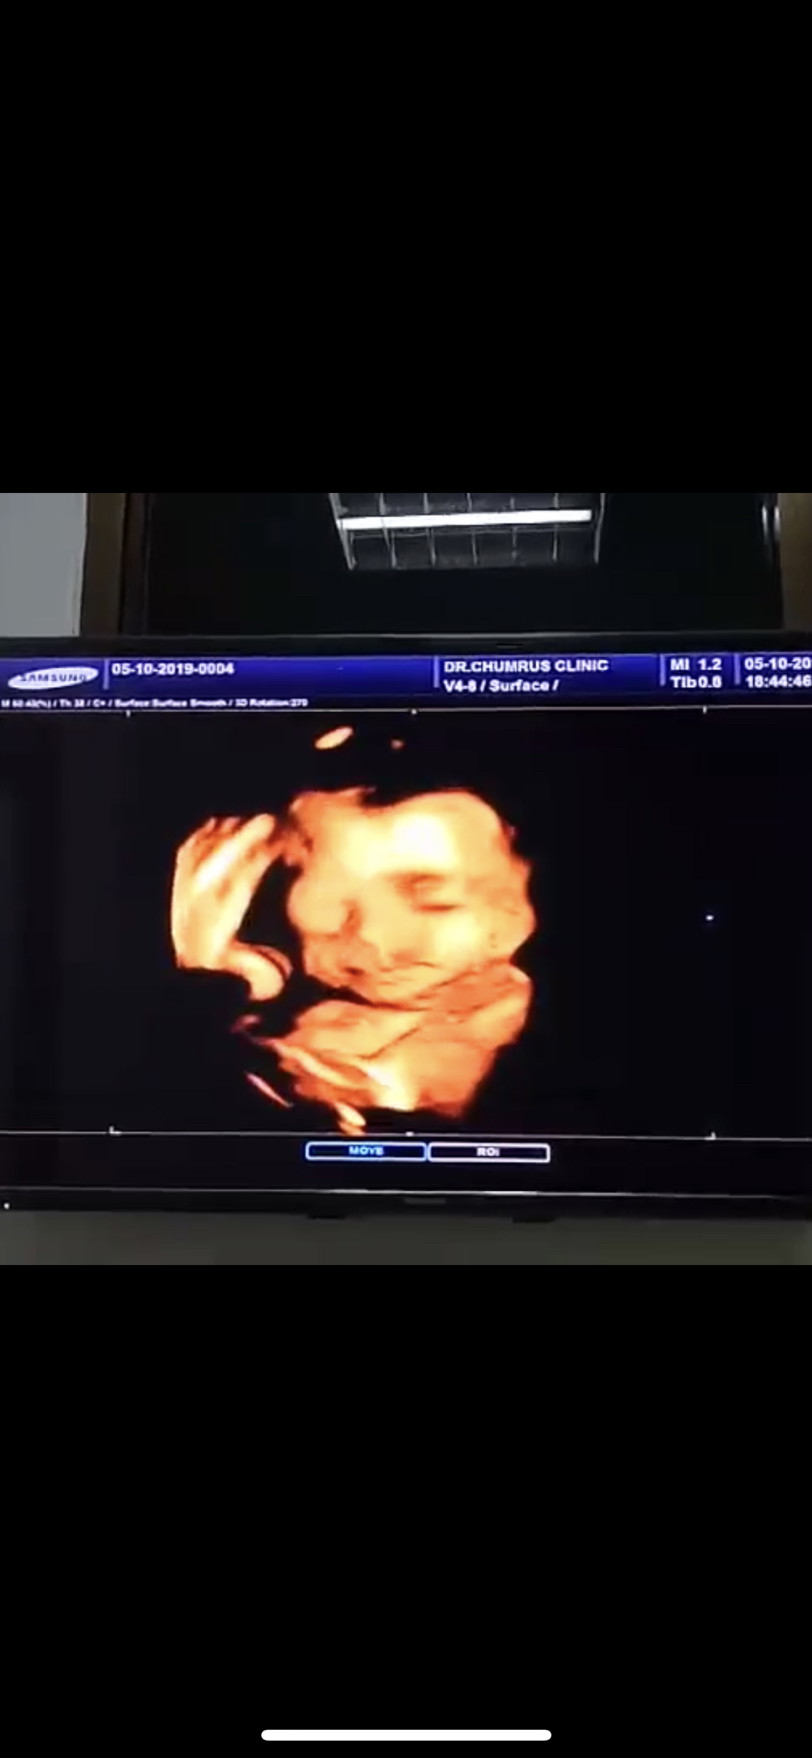

🎀

25 w

ในใบซาวด์25วีค5วันค่ะ